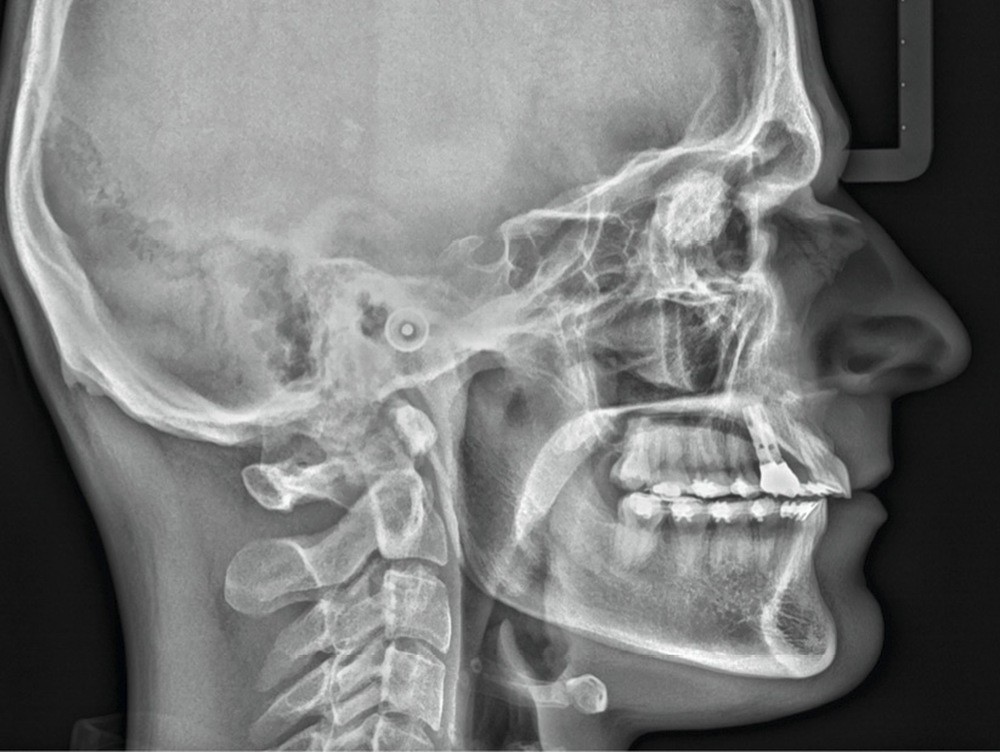

À l’examen de ces nouveaux clichés, une image radiologique de type « masse ronde » en regard des orbites se détache nettement. Immédiatement remontent mes souvenirs de cours de radio de l’examen du CECSMO. On nous apprenait à regarder la selle turcique et à reconnaître une tumeur. Une intime conviction s’impose : mon patient a une tumeur…

Je retourne immédiatement vers les premiers clichés avant traitement : l’image radiologique de la masse était déjà là !

Le volume semble identique, ce qui me rassure néanmoins sur le caractère peu évolutif. Je consulte sa fiche médicale, mais aucun problème de santé n’est mentionné.